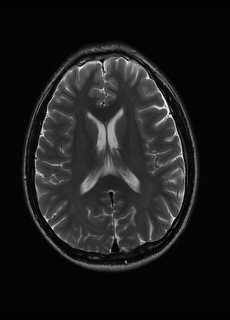

As we observe from the right image in Fig. 2, our BRM, both from MIMO and SISO settings, predicts the performance of dedicated models with a high correlation. We further choose the best three , and perform the last stage of fine-tuning accordingly to (6). A visual evaluation on real data is shown in Fig. 3. For simulated data, please refer to the Supplemental Material section.

Base on the best performing , we perceive that among , , and FLAIR, the results are best when is sampled the most. We suggest that this makes intuitive sense as images provide the best contrast out of the three sequences, which can compensate for the details lost in other images. The same observation can be made on the simulated data, where both and FLAIR show good contrast. When the time setting is changed to non-uniformity, we can see that our search for the best sampling strategy reflects the change. is sampled more as a result of faster acquisition time, while is still sufficiently sampled.

| Sequence | LR | SISO | MIMO | MIMO tuned | GT |

|---|---|---|---|---|---|

(a) 34.38/0.9371

(a) 34.38/0.9371

|

(b) 42.42/0.9883

(b) 42.42/0.9883

|

(c) 44.60/0.9920

(c) 44.60/0.9920

|

(d) 45.50/0.9940

(d) 45.50/0.9940

|

(e) PSNR/SSIM

(e) PSNR/SSIM

|

|

(f) 29.74/0.8903

(f) 29.74/0.8903

|

(g) 36.25/0.9734

(g) 36.25/0.9734

|

(h) 36.42/0.9752

(h) 36.42/0.9752

|

(i) 37.70/0.9832

(i) 37.70/0.9832

|

(j) PSNR/SSIM

(j) PSNR/SSIM

|

|

(k) 39.89/0.9311

(k) 39.89/0.9311

|

(l) 43.94/0.9864

(l) 43.94/0.9864

|

(m) 44.74/0.9883

(m) 44.74/0.9883

|

(n) 45.49/0.9894

(n) 45.49/0.9894

|

(o) PSNR/SSIM

(o) PSNR/SSIM

|